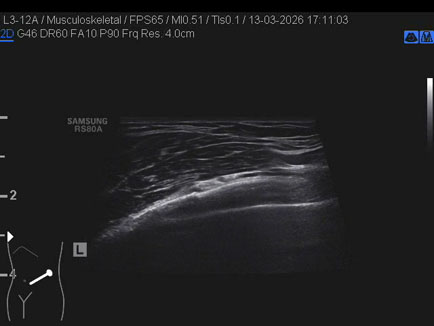

Data inserimento: 23/03/2026

Ecografia del: 13/03/2026

Strumento: Samsung

Sonda: Lineare

Commento all'esame: triplice frattura costale in ascellare anteriore sinistra in giovane dopo caduta con gli sci.

Conclusioni: triplice frattura costale (triple rib fracture).

Realizzazione: Dr. F. Pietro Tarini - Gubbio (PG)